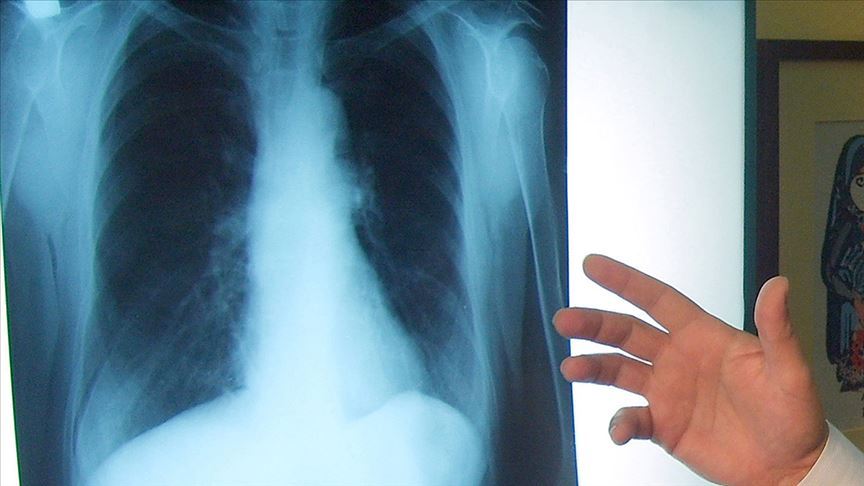

AKCİĞER KANSERİNDE YENİ TEDAVİ YÖNTEMLERİ SAĞ KALIM SÜRESİNİ ARTIRIYOR

Bilim insanları, akciğer kanseri tedavisinde kemoterapinin yanı sıra hedefe yönelik tedavi ve bağışıklık sisteminin harekete geçirildiği immüno-onkoloji uygulamalarının yer almasıyla sağ kalım süresinin ve yaşam kalitesinin arttığını belirtti.

Bilim insanları, akciğer kanseri tedavisinde kemoterapi ile hedefe yönelik tedavi ve bağışıklık sisteminin harekete geçirildiği immüno-onkoloji uygulamalarının hastalarda sağ kalım süresi ve yaşam kalitesini artırdığını bildirdi.

Türk Tıbbi Onkoloji Derneği Yönetim Kurulu Üyesi Doç. Dr. Özlem Sönmez, AA muhabirine yaptığı açıklamada, akciğer kanserinin hem Türkiye'de hem dünyada, kansere bağlı yaşam kayıplarının ilk nedeni olduğunu söyledi.

Dünyada bir yılda ortaya çıkan yeni akciğer kanseri vaka sayısının 2 milyon 900 bin ve buna bağlı yaşam kaybının 1 milyon 79 bin olduğu bilgisini veren Sönmez, "Türkiye'de her yıl 30 bin yeni akciğer kanseri vakası görülmektedir." dedi.

Kanser tedavisinde yeni bilimsel çalışmaların sonuçlarının açıklandığını ve önemli kazanımlar elde edildiğini anlatan Sönmez, günümüzde kansere neden olan gen değişikliklerini hedefleyen ve vücudun savunma sistemi hücrelerini devreye sokacak onlarca molekül ile ilgili klinik çalışmaların da sürdürüldüğünü dile getirdi.

Akciğer kanserinin en yeni gelişmelerin olduğu ve en yeni tedavilerin kullanıldığı kanser türü olduğunu vurgulayan Sönmez, tümörün genetik haritasının çıkarılmasıyla kişideki kansere neden olan genetik değişiklik bulunarak, o geni etkisiz hale getiren en uygun tedavinin belirlenebildiğini aktardı.

Sönmez, halk arasında "akıllı ilaçlar" veya "sihirli mermiler" olarak isimlendirilen ilaçların başarı oranının yüksek olduğunu ifade ederek, "Eskiden vücuda yayılmış evre akciğer kanseri hastaları 1 yılın altında yaşarken, bu ilaçları kullanabildiğimiz hastalar uzun yıllar aktif yaşamlarını sürdürebiliyor." diye konuştu.

Yeni tedavi seçeneklerinde vücudun bağışıklık sisteminin harekete geçirildiği immüno-onkolojinin önemli yer tuttuğuna işaret eden Sönmez, "Kemoterapi ile tümör hedef alınıyor. İmmüno-onkolojik tedaviler kemoterapiden farklı olarak bağışıklık sistemini güçlendiriyor. Vücudun savunma sistemi hücrelerini, yani komandolarını harekete geçirerek tümörü yok etmeyi amaçlıyor. Bu nedenle yan etkileri de daha az ve kontrol edilebilir düzeyde oluyor." ifadelerini kullandı.

Vücudun savunma sistemi hücreleri olan T hücreleri aktif bile olsa kanserli hücre saldırısını frenleme yönünde bir sinyal alındığında kanserli hücreyi öldürmediğini, geri çektiğini bildiren Sönmez, şunları kaydetti:

"Bu nedenle frenlenmeyi ortadan kaldıran ve 'immun kontrol noktası inhibitörleri' olarak isimlendirilen ilaçlar geliştirildi, immün kontrol noktası molekülü tanımlandı. Bu ilaçlardan üçünün akciğer kanseri tedavisinde kemoterapi ile veya tek başına akciğer kanseri tedavisinde etkinliği ve güvenilirliği çok sayıda çalışma ile gösterildi ve sonuçları saygın tıp dergilerinde yayımlandı. Dünya Akciğer Kanseri Kongresi'nde, immüno-onkoloji tedavisinde yeni bir ajan olan 'atezolizumab' etken maddeli ilacın sonuçları ele alındı. Kemoterapiye atezolizumab etken maddeli ilaç tedavisinin eklenmesi ile yassı hücreli tip akciğer kanseri tanılı hastalarda genel sağ kalım süresine yaklaşık 13 ay daha katkı sağlandığı gösterildi.

Yine kongrede, metastatik evre küçük hücreli akciğer kanserinde, kemoterapi ile birlikte bir diğer immüno-onkoloji tedavi ilacı 'durvalumab' etken maddeli ilacın kemoterapiye eklenmesi ile genel sağ kalıma 3 ay eklendiği ve tedavi cevap oranının bu hastalarda daha iyi olduğu ortaya konuldu."

Türk Akciğer Kanser Derneği Başkanı Prof. Dr. Erdem Göker de akciğer kanserinin farklı tipleri olduğunu hatırlatarak, "Bugün geldiğimiz noktada, her çeşit akciğer kanserinin tedavisi için farklı yaklaşım ve ilaçlar bulunmaktadır. En doğru tedavi, akciğer kanseri ile uğraşan değişik dallardaki uzmanların ortak çalışması ile bulunmakta ve aynı anda birden çok yöntemin eş-güdümle kullanılması ile imkansız görünen başarıya ulaşılmaktadır." değerlendirmesinde bulundu.

Akciğer kanseri tanı ve tedavisinde uygulanan yöntemlerin özellikle son 5 yıl içinde tamamen değiştiğine dikkati çeken Göker, şu bilgileri verdi:

"Daha doğru ve kesin tanı için, yepyeni araç ve gereçler geliştirildi, hastaya eziyet çektirmeyen, konforunu bozmayan yöntemler kullanılmaya başlandı. Bu tanı yöntemleriyle, tümörün moleküler genetiği deşifre edildi. Cerrahi ve radyasyon onkolojisinde tarih, akciğer kanseri için yeniden yazılmaya başlandı. En az doku kaybı ve hasarı, dolayısıyla önemsenmeyecek yan etkilerle birlikte başarı şansı en üste çıkmaya başladı. Her iki uzmanlık alanında da yine uzay teknolojisi kullanılmaya başlandı. Kapalı ameliyatlar ve nokta atışlı ışın tedavileri ülkemizde de hızla yerini almaya başladı.

Hedefe yönelik tedavi ve immünoterapi devrim niteliğinde ilerlemedir. Bunlardan birincisi, sadece kanser hücresini etkileyen ve öldüren ilaçlar olan hedefe yönelik tedavi. İkinci tedavi yöntemi ise kansere bakış açımızı sil baştan değiştiren immünoterapi oldu. Kanser hücrelerini akıllı yapanın, bağışıklık sistemini aptallaştırabilme yeteneği olduğunu ortaya koyan iki bilim insanı, Nobel ödülü aldı. Kanser hücrelerinin bu yeteneği anlaşıldıktan sonra, savaşımız bunlara yöneldi ve immünoterapi tedavisi geliştirildi. Ülkemizde çoğu onkoloji merkezinde hem hedefe yönelik tedaviler hem immünoterapiler başarıyla uygulanıyor. Sağlık Bakanlığınca bu tedavilerin kullanımı onaylandı, Sosyal Güvenlik Kurumunca bu ilaçların geri ödeme kapsamına alınmasını umuyoruz."

Dünya genelinde erkekler arasında en sık görülen kanser türü olan akciğer kanseri, kadınlarda da üçüncü sırada yer alıyor.

Akciğer kanseri Türkiye'de de kanserden kaynaklanan ölümlerin en yaygın nedeni olarak belirtiliyor. Türkiye'de erkeklerde nefes borusu, bronş ve akciğer kanseri ilk sırada, kadınlarda ise bu kanser türü en sık görülen beşinci kanser türü olarak yerini alıyor.

Türkiye'de ortalama tanı alma yaşı 64 olurken, 40 yaşın altındakilerde akciğer kanseri daha nadir görülüyor ve genellikle ileri evrelerde teşhis ediliyor.